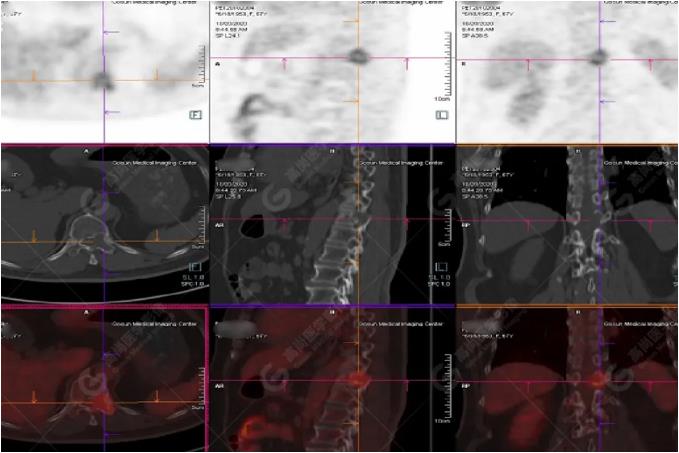

女性 67歲 因背痛查體,糖尿病11年。腫瘤標(biāo)記物:CEA 6.4↑,AFP、CA125、CA199正常。外院MR檢查:胸11椎體-附件左份異常信號(hào),增強(qiáng)環(huán)狀強(qiáng)化,骨原發(fā)?轉(zhuǎn)移?感染?PET/CT影像圖

胸椎溶骨性骨質(zhì)破壞,F(xiàn)DG環(huán)狀代謝增高,SUVmax為4.0。

左側(cè)乳腺一軟組織結(jié)節(jié),F(xiàn)DG代謝增高,SUVmax為2.6。

最終診斷:左側(cè)乳腺癌伴胸椎單發(fā)骨轉(zhuǎn)移。